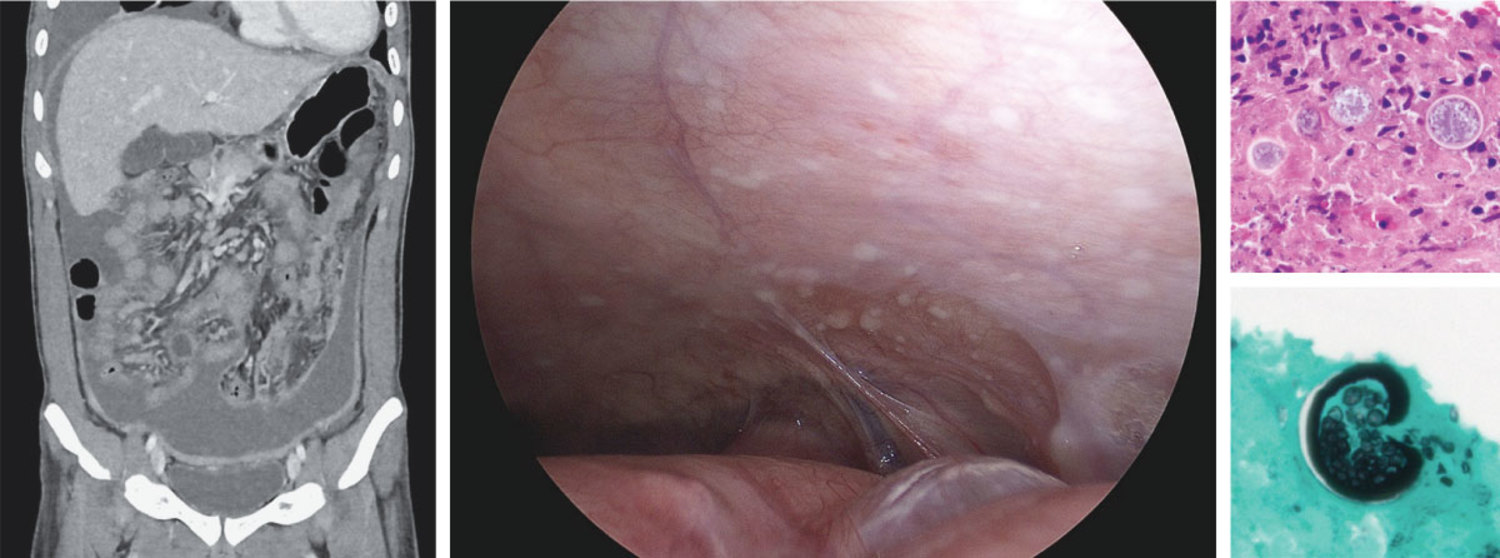

A 23-year-old man presented to the emergency department with a 2-month history of unintentional weight loss and worsening abdominal pain and distension. The patient had recently moved to Arizona from a remote Pacific Island. Physical examination was notable for a firm abdomen with diffuse tenderness to palpation. A diagnostic laparoscopy revealed peritoneal nodules and inflammatory adhesions. A peritoneal biopsy and computed tomography of the chest, abdomen, and pelvis are shown. Which of the following is the most likely etiology of the peritoneal nodules?

一名23岁男性因“无意识体重减轻2个月,伴腹部疼痛和腹胀逐渐加重”到急诊科就诊。患者最近从偏远的太平洋岛屿搬到亚利桑那州。体格检查发现腹部触之质硬,并有弥漫性压痛。诊断性腹腔镜检查显示腹膜有结节和炎性粘连。腹膜活检及胸、腹、盆腔CT结果如图所示。以下哪项最可能是这些腹膜结节的病因?

腹膜活检的组织病理学分析显示:坏死性肉芽肿,伴大型厚壁球形体(spherules);腹膜组织的真菌培养生长出球孢子菌(Coccidioides)。最终诊断为腹膜球孢子菌病。给予长期氟康唑治疗。出院后1个月随访,患者症状已缓解。